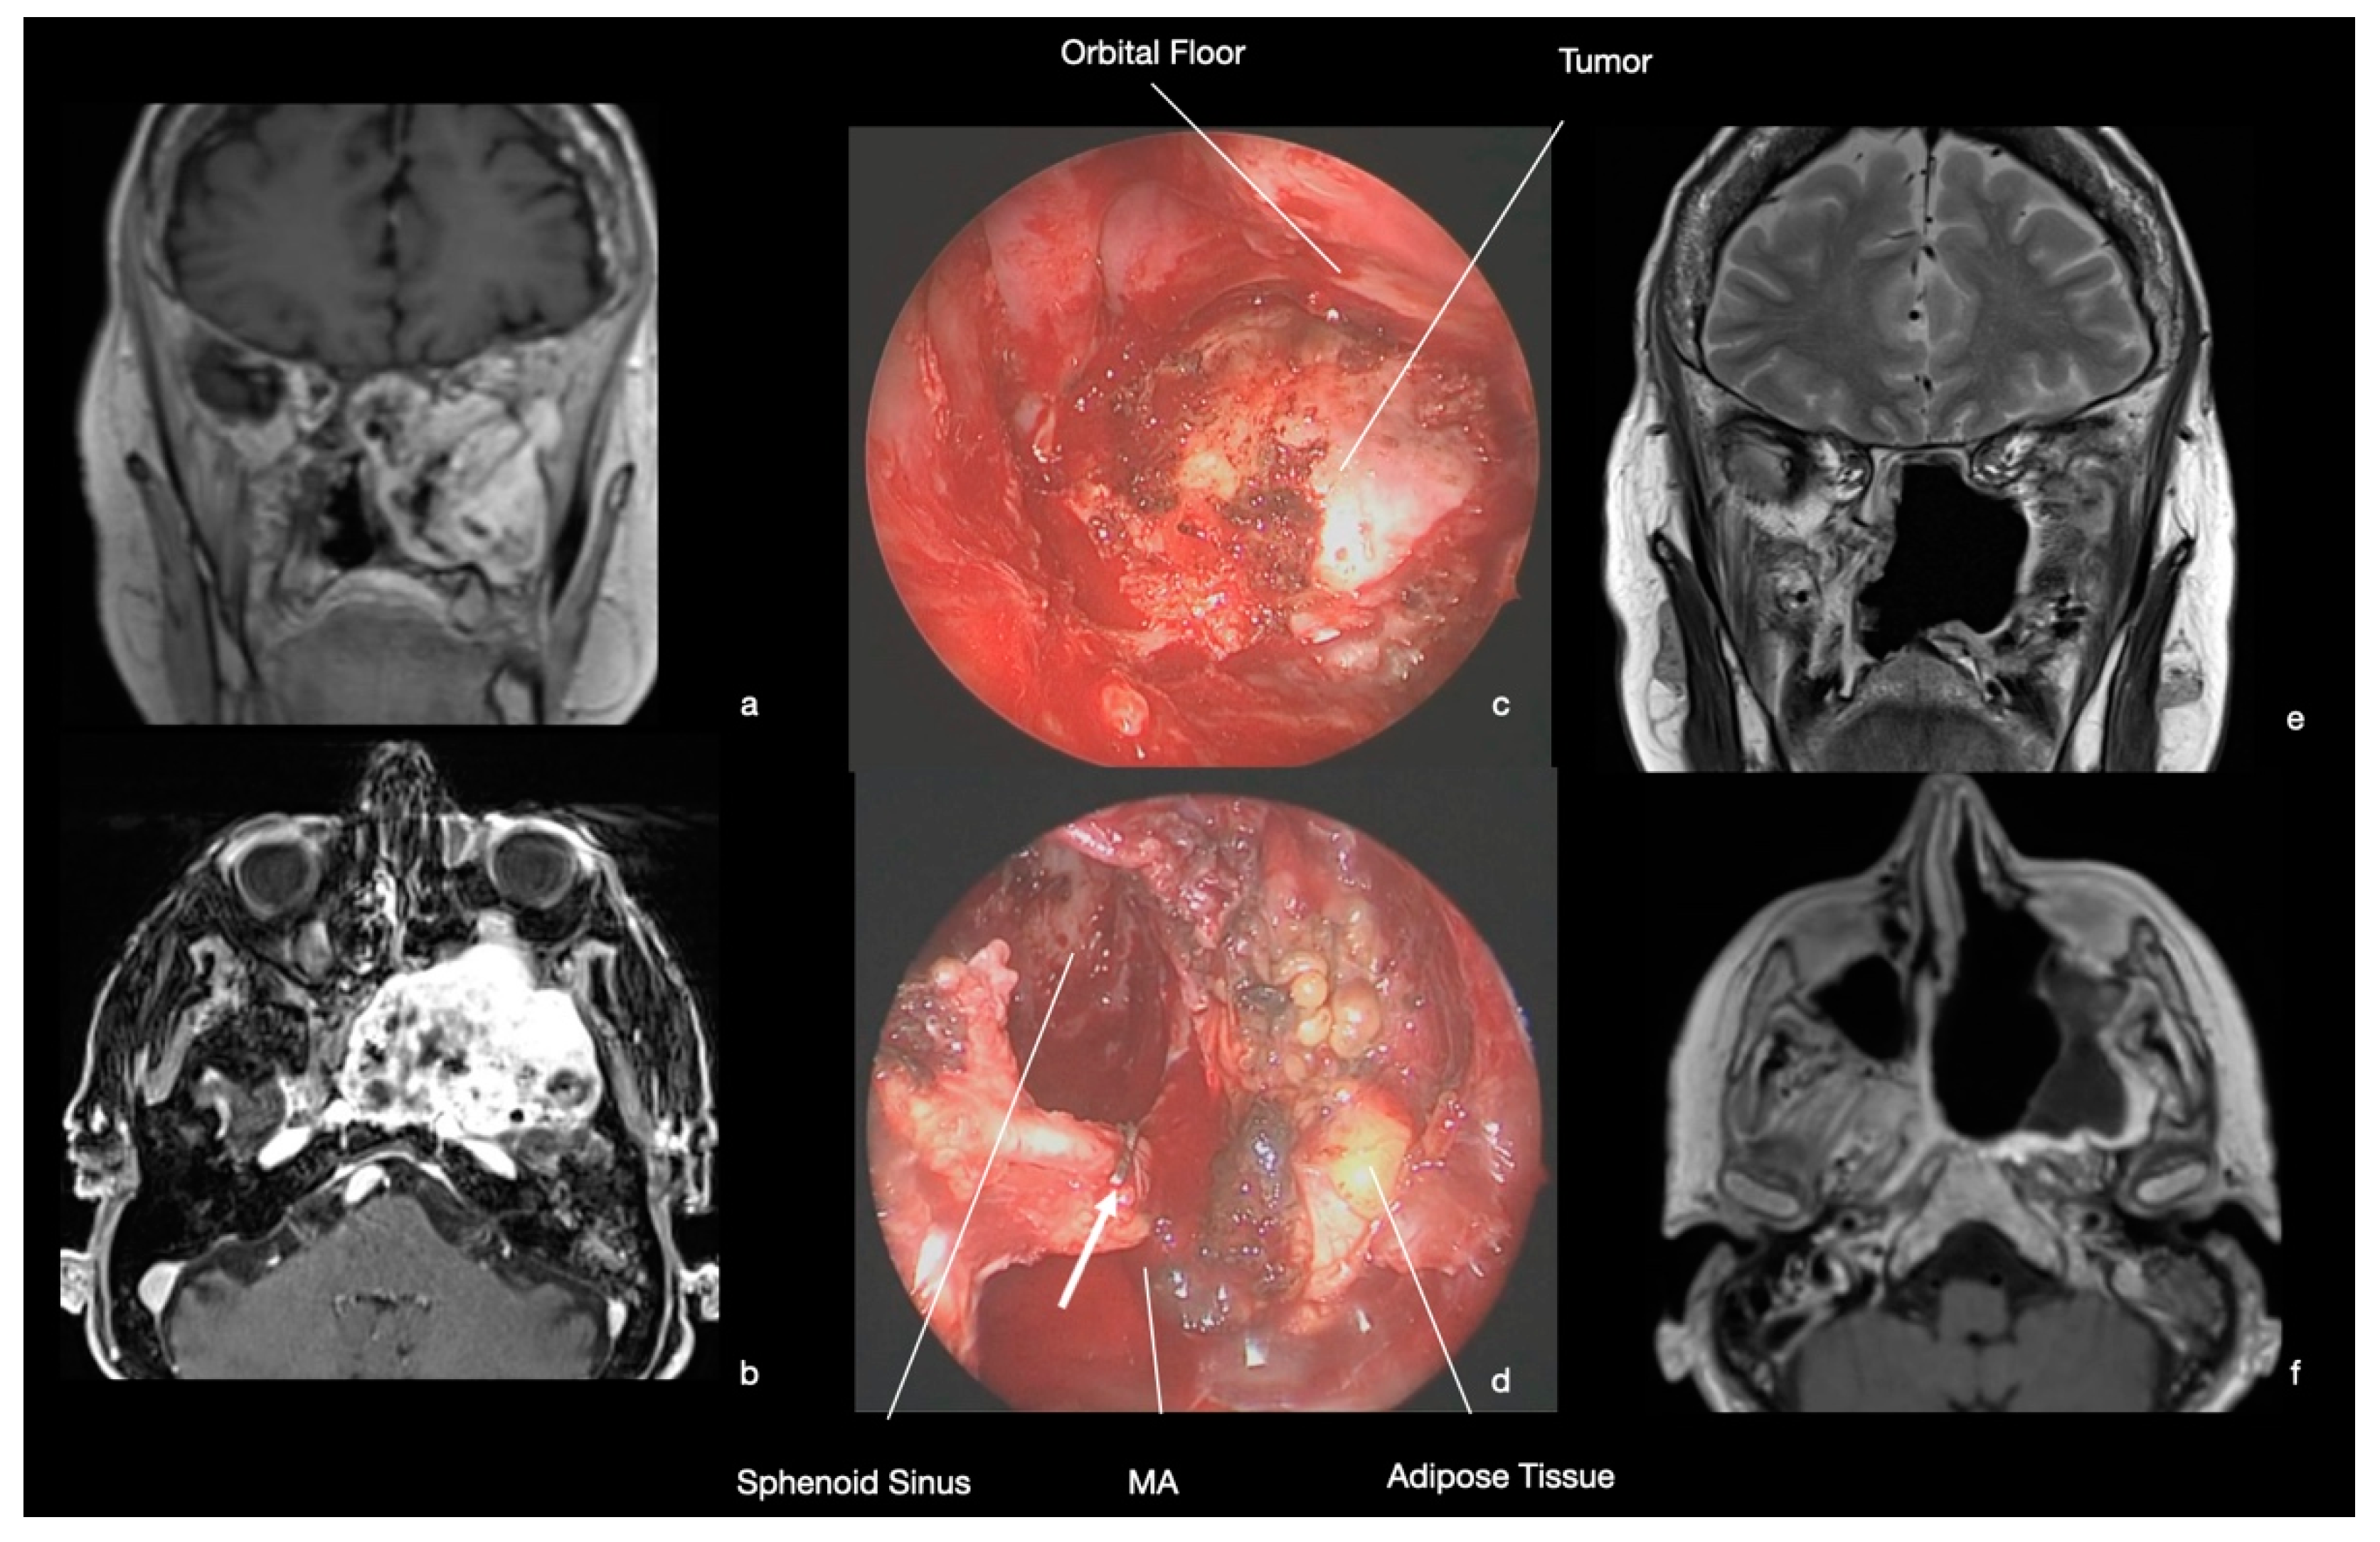

9.3. Case 3